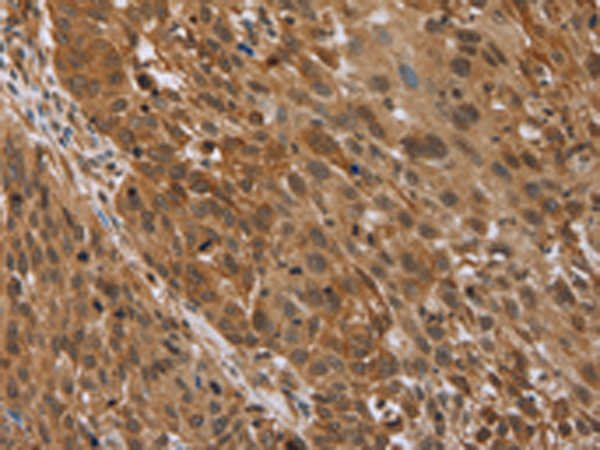

分类: 科研抗体货号: P11014别名: sMAP; MAP19; MASP-2; MASP1P1应用: IHC反应种属: Human, Mouse, Rat